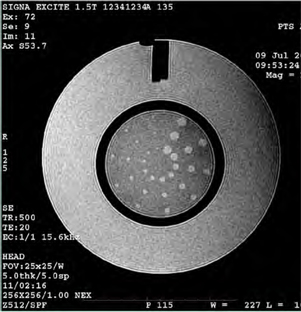

Slice Position Accuracy

The slice position accuracy test assesses the accuracy with which slices can be prescribed at specific locations utilizing the localizer image for positional reference.

Slices 1 and 11 were prescribed to be aligned with the vertices of the crossed 45 degree wedges at the inferior and superior ends of the phantom respectively. On the images of slices 1 and 11 the crossed wedges appear as a pair of adjacent, dark vertical bars at the top (anterior side) of the phantom. See illustration below. A perfectly positioned slice’s image shows a dark bar pair with left and right sides of equal vertical length. If the slice is displaced superiorly with respect to the vertex, the bar on the observer’s right (anatomical left) is longer. If the slice is displaced inferiorly with respect to the vertex, the bar on the left (anatomical right) will be longer.

Referring to Figure 18, use the on-screen length measurement tool to measure the difference in vertical lengths between the left & right bars of the cross wedge in mm.

Record the difference (as a negative value if the left bar is longer) as ACR T1 Slice 1 Bar Length Difference (mm). Use the ACR Accreditation Scan Measurements form to record the values.